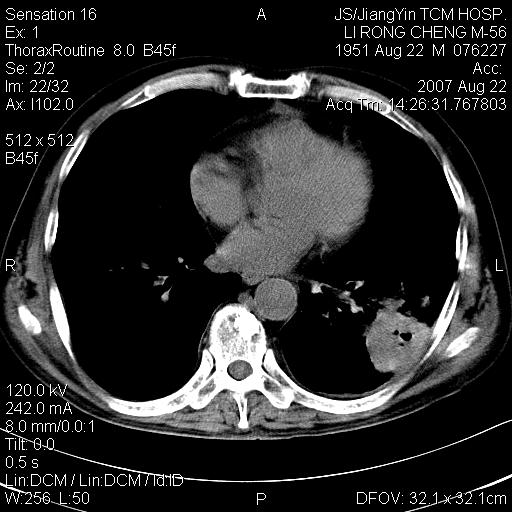

标题: CT9479:M,56Y,DM病史,咳嗽发热5天.肺脓疡.肺癌? [打印本页]

标题: CT9479:M,56Y,DM病史,咳嗽发热5天.肺脓疡.肺癌?

边灶边缘较光整,冠状位病灶呈大片状,,内有空洞,有胸膜反应,但无明显胸膜外侵犯征像,结合病史支持考虑肺肿脓,不排除结核,治疗后复查

好多钙化灶哦,病灶位于下叶背段,或许考虑结核更合适,做下相应检查先

左肺下叶见类软组织密度影,其内密度不均,有小空洞,广基与胸膜相连,其周见斑片状致密影.

考虑肺肿脓,不排除结核.

左肺下叶支气管呈小囊状扩张。下叶背段有类圆形高密度影,边缘模糊,外与胸膜相连。左侧胸膜增厚粘连。心包膜增厚。结合病史考虑1支扩并感染2胸膜及心包炎。

左下肺团片状类软组织密度影,形态不规则,边缘欠规整,其内可见液化区及气体影,病灶内侧见引流支气管影,相邻胸膜反应性增厚。病灶周围肺野内见增粗支气管,壁厚,边缘模糊。考虑:支气管扩张并感染;肺脓肿。